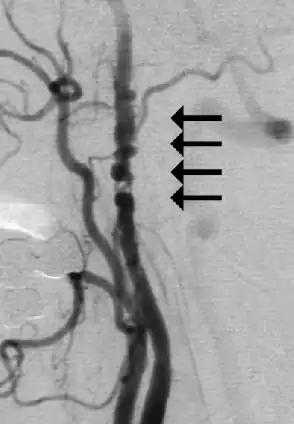

Angiogram showing narrowing of the arteries in the neck in a women with a TIA[1] | |